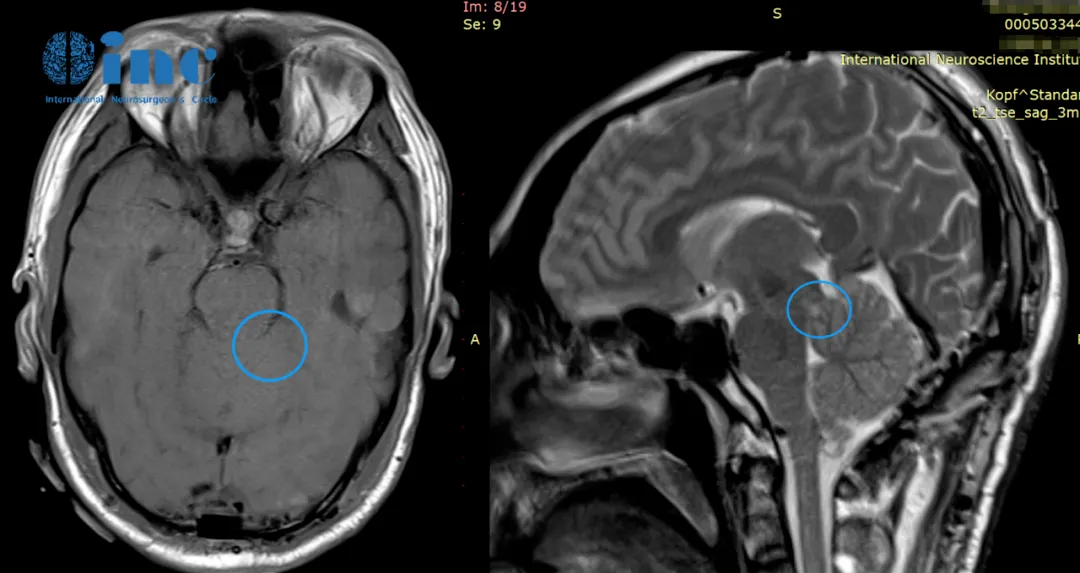

33岁的周老师,因频繁头痛头晕就医核磁共振检查结果显示中脑背侧占位,病变大小约1cm,考虑为低级别胶质瘤可能大。因为病变位于脑干,手术风险极大,术中稍有差池都可能直接造成高位瘫痪,国内就医后被建议谨慎考虑治疗方案或选择保守治疗。

赴德治疗过程:2020年成功接受手术,诊断为左侧脑干(中脑顶盖区)的低级别胶质瘤。手术过程:半坐位,经显微镜下全切肿瘤,术中全程电生理监测,手术顺利无神经缺损。术后第1天迁出ICU,回到普通病房,周先生可在普通病房自行用餐,术后第2天,周先生在医护人员的帮助下下床行走。术后第5天,周先生顺利出院。在这样的“手术禁区”,不但没有发生严重的、不可逆的神经损伤甚至可以说几乎没有什么症状,并没有在ICU多留,术后第五天竟然就能出院了,“就像做了个小手术一样”。